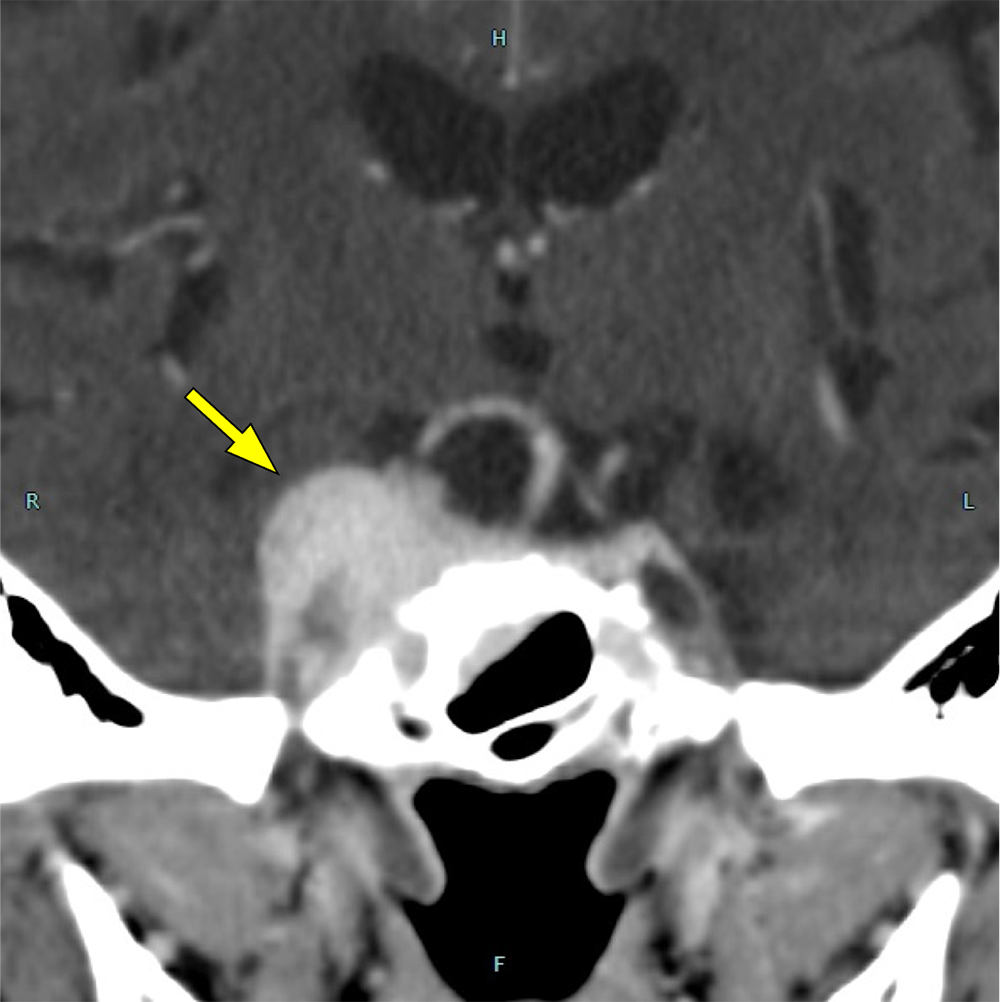

図1.単純CT

右海綿静脈洞に脳実質と等吸収の腫瘤を認める。